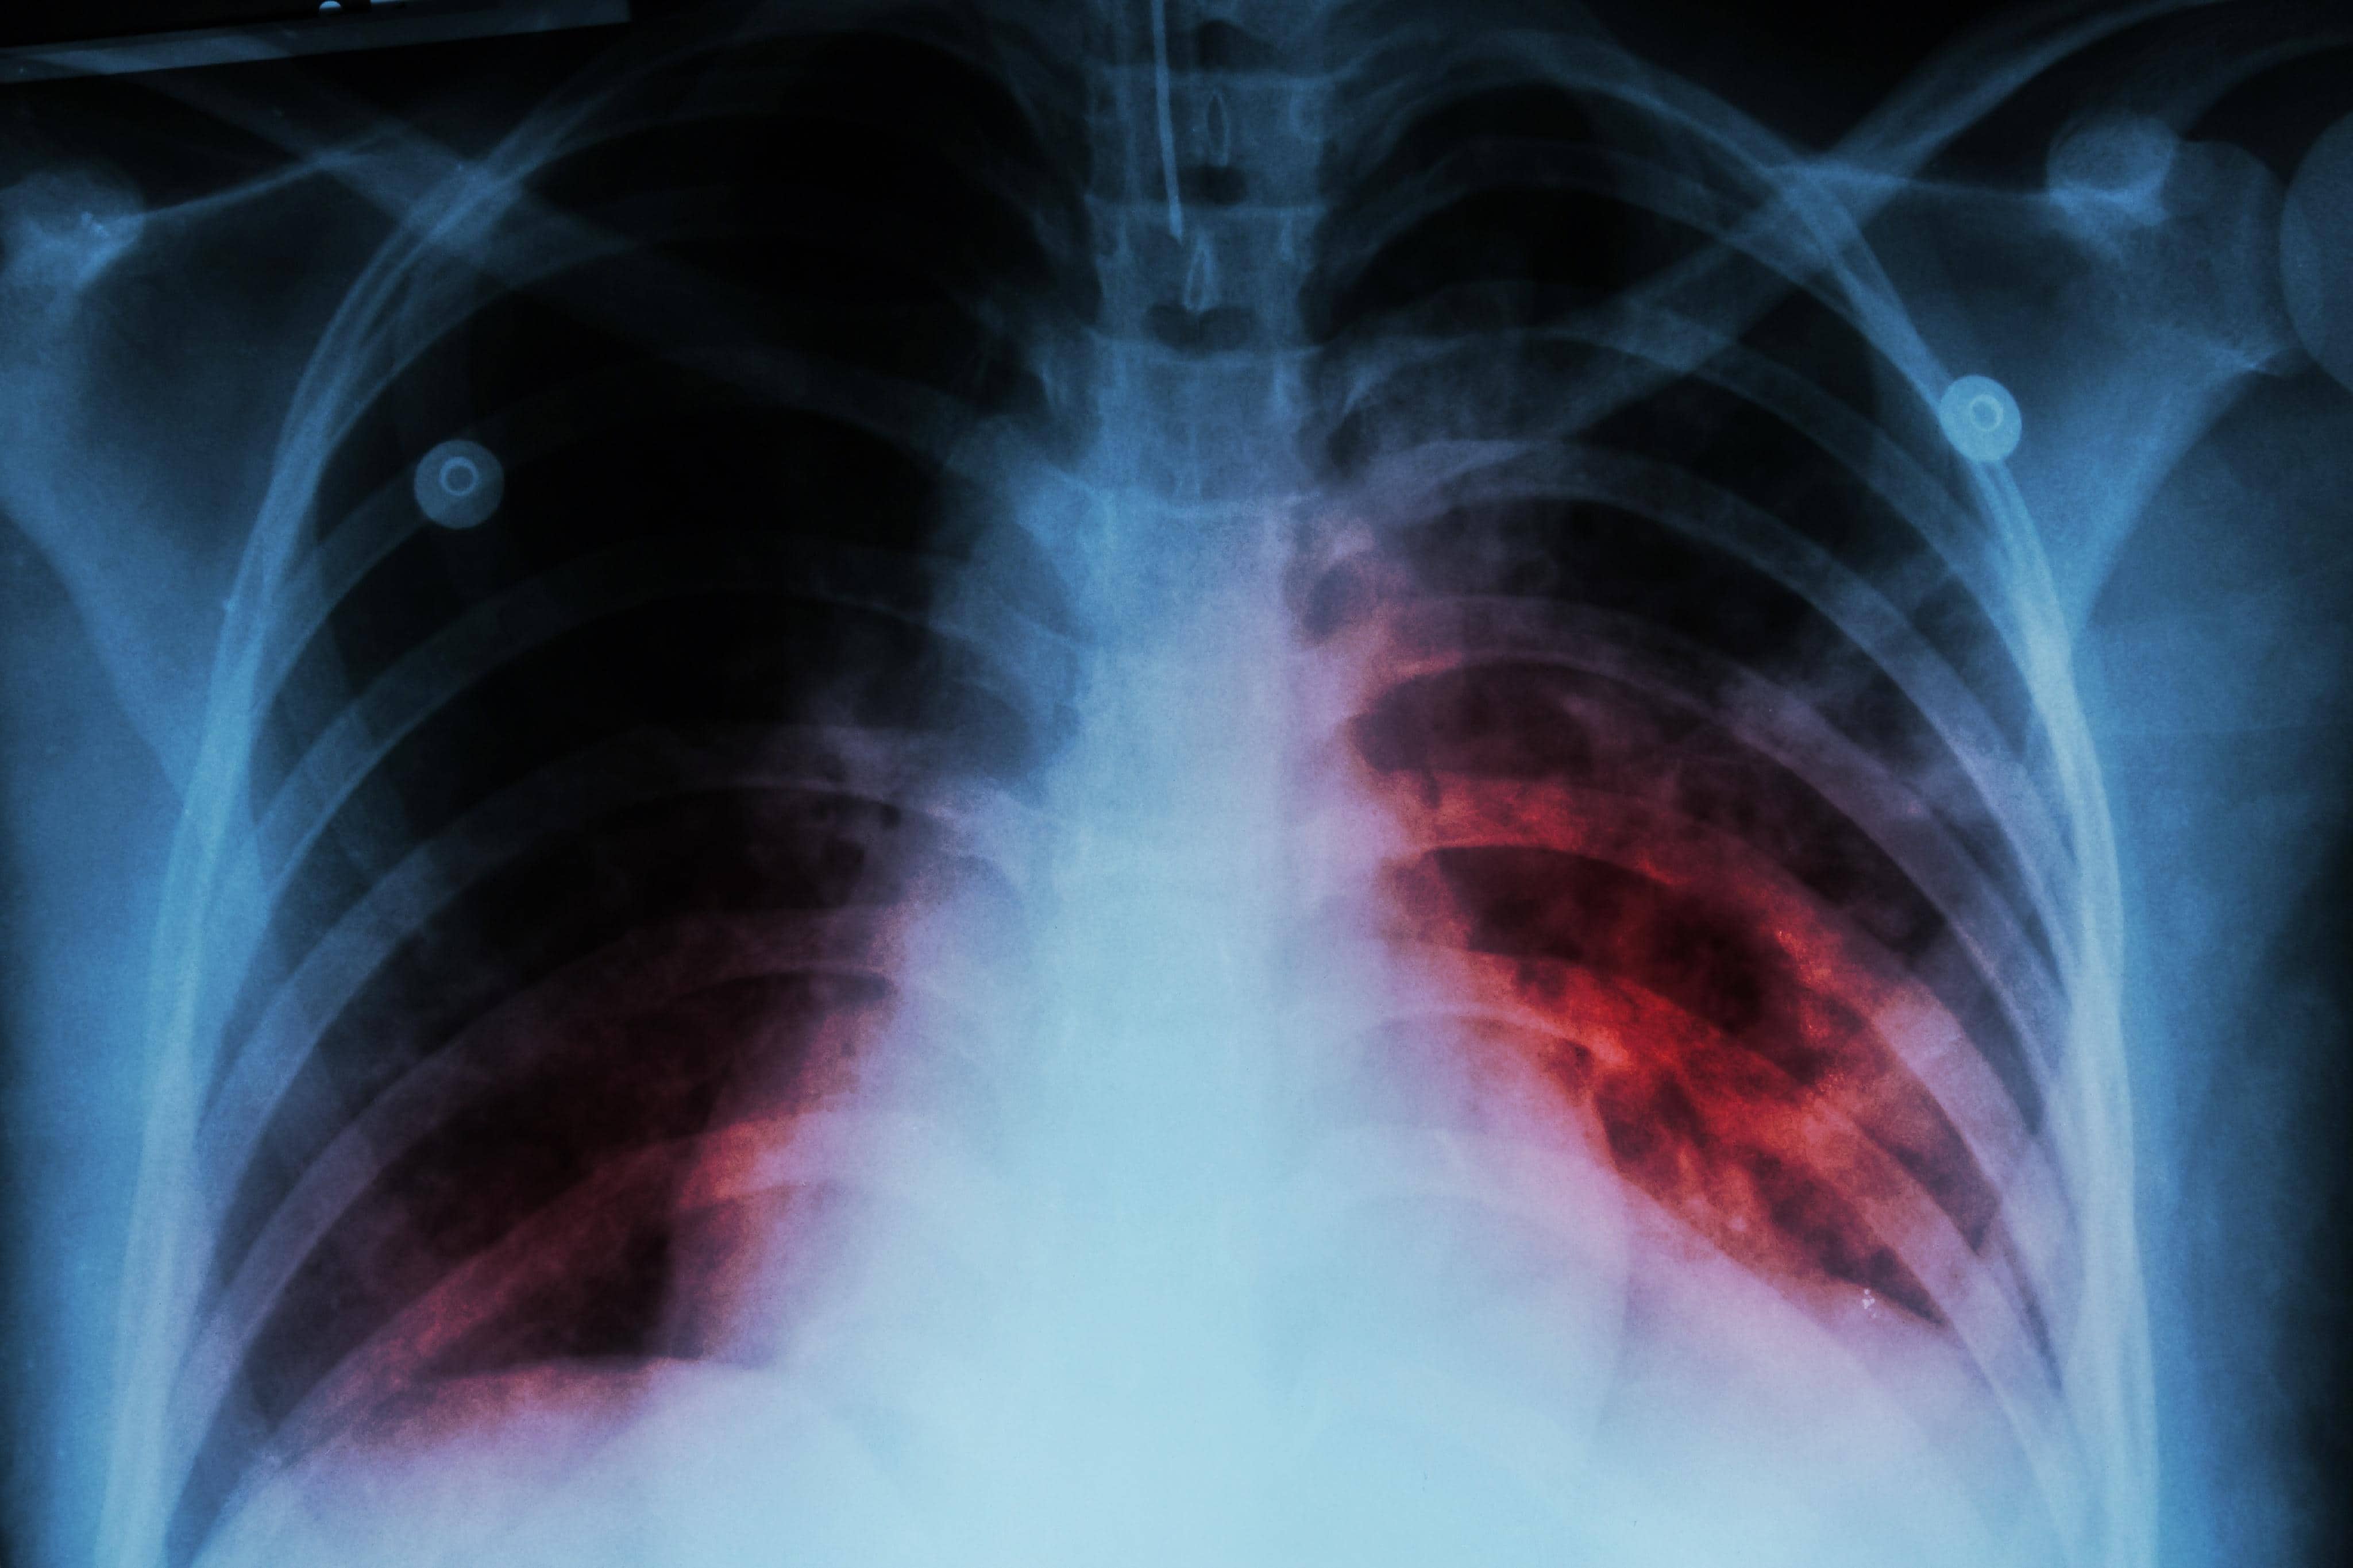

PIEDRAS NEGRAS, COAH.– La Jurisdicción Sanitaria 01 informó que, de enero a la fecha, se han detectado cinco pacientes con diagnóstico positivo de tuberculosis, quienes ya iniciaron tratamiento como parte de las acciones de vigilancia epidemiológica y detección oportuna de esta enfermedad.

Zayuri Cázares Escareño, responsable del programa de Micobacteriosis, explicó que los casos corresponden a pacientes sintomáticos respiratorios, es decir, personas que presentan tos persistente por más de dos semanas, uno de los principales signos de alerta.

Indicó que el personal médico identifica a personas con síntomas respiratorios prolongados y las canaliza al área correspondiente para su evaluación y seguimiento. Como parte del protocolo diagnóstico, la Jurisdicción Sanitaria aplica pruebas de PPD y realiza estudios de imagen.